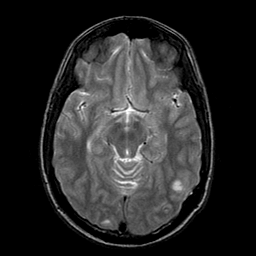

Sarcoma, MR Study #1 mr-t2 -- Slice #9

[Home][Help][Clinical] Slice 9